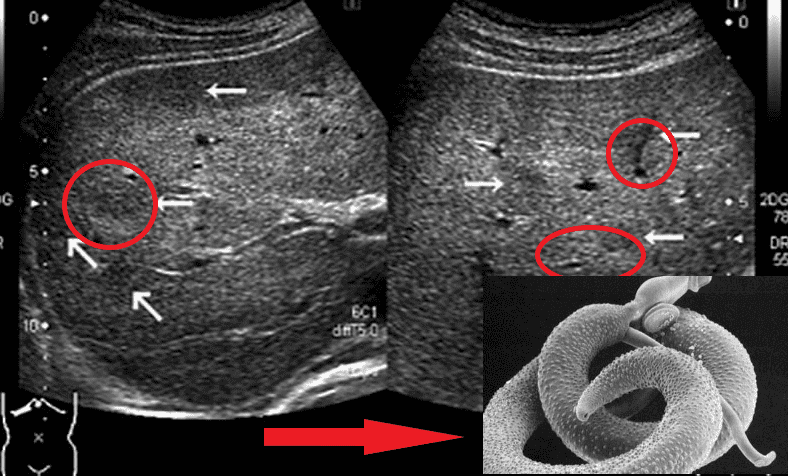

На фото нижче можете побачити знімок кишечника. Пацієнтка померла від раку кишківника, спричиненого паразитами. Паразити отруюють здорові клітини своїми токсинами, через що вони змушені перероджуватися, змінювати свою структуру. І перероджуються вони саме в ракові клітини, які агресивніші й здатні протистояти паразитам. Але для людини ці клітини згубні. Пухлина швидко розвивається і метастазує. Людина гине протягом лічених місяців.

"Ходи" паразитів у просвіті кишечника

Представниками гельмінтів, що вражають життєво важливі органи, є Taenia solium, ехінокок (Echinococcus granulosus), трихінела (Trichinella spiralis). Ехінокок являє собою личинкову стадію гельмінта з роду Echinococcus. І це далеко не всі види паразитів, здатні убити людину.